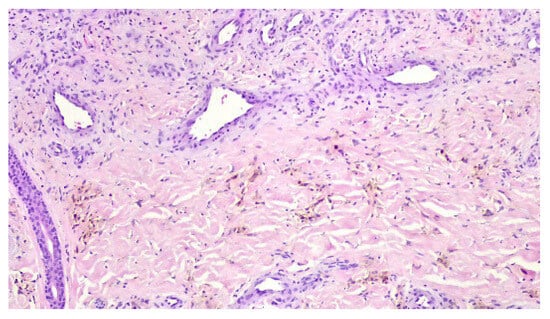

Collision Tumor of Angioimmunoblastic T-Cell Lymphoma and Kaposi Sarcoma in an HIV-Negative Elderly Woman: The First Reported Case in Asia

by Myung-Won Lee and Jin-Man Kim

Diagnostics 2025, 15(18), 2411; https://doi.org/10.3390/diagnostics15182411 - 22 Sep 2025

Background/Objectives: Angioimmunoblastic T-cell lymphoma (AITL) is a rare peripheral T-cell lymphoma of follicular helper T-cell (TFH) origin, often associated with immune dysregulation and EBV-positive B-cell proliferation. Kaposi sarcoma (KS) is a vascular neoplasm caused by human herpesvirus 8 (HHV-8), typically arising in immunocompromised [...] Read more.

Background/Objectives: Angioimmunoblastic T-cell lymphoma (AITL) is a rare peripheral T-cell lymphoma of follicular helper T-cell (TFH) origin, often associated with immune dysregulation and EBV-positive B-cell proliferation. Kaposi sarcoma (KS) is a vascular neoplasm caused by human herpesvirus 8 (HHV-8), typically arising in immunocompromised individuals. The synchronous occurrence of AITL and KS in HIV-negative patients is exceptionally rare, with only three cases previously reported worldwide. Case Presentation: We describe an 81-year-old HIV-negative Korean woman presenting with progressive generalized edema and dyspnea. Imaging revealed multifocal lymphadenopathy. Excisional biopsy of the inguinal lymph node showed two distinct but adjacent neoplastic processes. The AITL component demonstrated a polymorphous infiltrate of atypical TFH cells expressing CD3, CD4, CD10, PD-1, and Bcl-6, with monoclonal TCR-γ rearrangement and TET2 and RHOA mutations. The KS component comprised spindle cells with slit-like vascular spaces, red blood cell extravasation, and immunoreactivity for HHV-8, CD31, CD34, and ERG. The findings were consistent with a collision tumor. Despite supportive care, the patient’s condition deteriorated, and she was discharged with palliative care. Discussion: The coexistence of AITL and KS in an HIV-negative setting raises important pathogenetic considerations. AITL is characterized by profound immune dysregulation, with depletion of normal T-cell subsets, abnormal B-cell activation, and cytokine milieu changes that may favor latent viral reactivation. This immunologic environment may permit HHV-8 reactivation, thereby facilitating the development of KS even in the absence of overt immunodeficiency due to HIV infection. Our findings support the hypothesis that AITL-related immune dysfunction may create a permissive niche for HHV-8-driven neoplasia. Conclusions: This is the first reported case in Asia and the fourth worldwide of a collision tumor comprising AITL and KS in an HIV-negative patI dient. The case suggests that AITL-associated immune dysregulation may facilitate HHV-8 reactivation and KS development even in the absence of HIV infection. Awareness of this association is critical for accurate diagnosis and optimal patient management. Full article